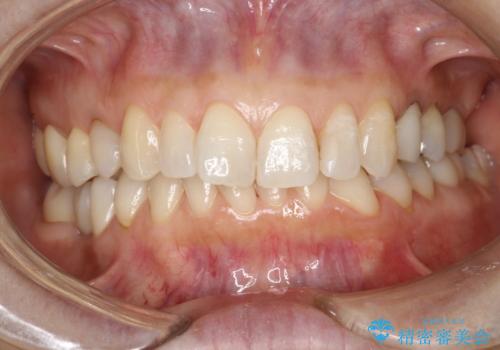

PMTCで歯と歯の間の細かいステインの除去

- 歯磨きでは取れない歯と歯の間の汚れが気になるとのことで来院されました。PMTC60分コースを行いました。

PMTCは、歯に付着した汚れを除去していくため、着色が気になる場合にも行うことができます。ご自身でのセルフケアだけで着色を落とそうとすると、逆に歯を傷つけてしまったり、精密に汚れを除去できないこともあります。また、日常生活で着色しやすい飲食物を避けたりすることはストレスに感じてしまったり、あまり現実的ではありません。

毎日丁寧に歯磨きをしていても、日常生活での飲食物などにより着色してしまうことはあります。PMTCでは、歯の表面の凸凹にミネラルを補給して、ツルツルの表面に仕上げます